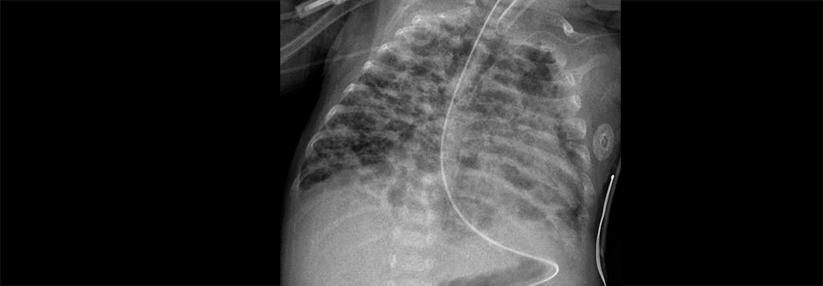

Definitionsgemäß liegt eine pulmonale Hypertonie ab einem mittleren pulmonal-arteriellen Druck von 20 mmHg vor. Das gilt sowohl für den prä- als auch für den postkapillären Hochdruck, erklärte Prof. Dr. Ekkehard Grünig von der Thoraxklinik am Universitätsklinikum Heidelberg. Welche Untersuchungen man zur weiteren Abklärung ansetzt, richtet sich danach, ob eine pulmonale oder kardiale Ursache vermutet wird. Generell hat aber der Ultraschall für die erste Beurteilung zentrale Bedeutung, unverzichtbar zur Diagnosesicherung ist ein Rechtsherzkatheter. Ein 3D-Echo hilft bei der Rechtsherzinsuffizienz oft nicht weiter, weil sich der vergrößerte rechte Ventrikel kaum erkennen lässt.